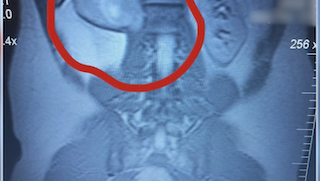

Avid runner Jason Smith didn’t want to slow down for a schwannoma spinal tumor. See how an innovative treatment plan got him back on track in less than six weeks.